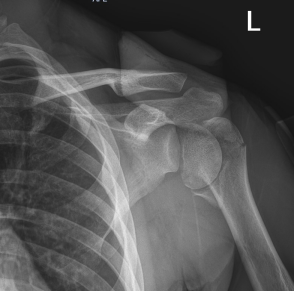

小李(化名)因骑车时不慎摔倒,左肩部着地,当即感到剧痛、肩关节畸形、无法活动。家人紧急将其送至西南医科大学附属天府医院急诊。影像学检查结果显示:肱骨近端碎成了4大块,肱骨头完全劈裂,翻转180°,卡在关节腔内,同时合并肩关节脱位。这一罕见而复杂的损伤,加之患者年轻,对肩关节功能恢复要求极高,治疗难度极大。

团队在仔细分析三维CT重建影像后,反复模拟手术路径,最终决定为小李实施切开复位Philos钢板内固定术,力求在彻底复位翻转肱骨头的同时,最大程度保护血液供应,重建肩关节功能。